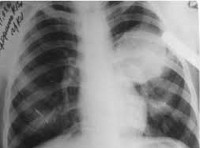

Клинические проявления при начальных стадиях заболевания обычно скудны, они выявляются, когда киста достигает значительных размеров или в связи со своим расположением сдавит важный орган и приведет к нарушению его функции. Эхинококковая киста внутренних органов (печень, почки, селезенка и ) обычно распознается, когда прощупывается тугоэластическая опухоль, а поражение легких, костей определяется на рентгеновских снимках в виде кистозных образований.

Эхинококкоз легких - второе по частоте проявление инвазии, может симулировать любое заболевание легких другой этиологии.